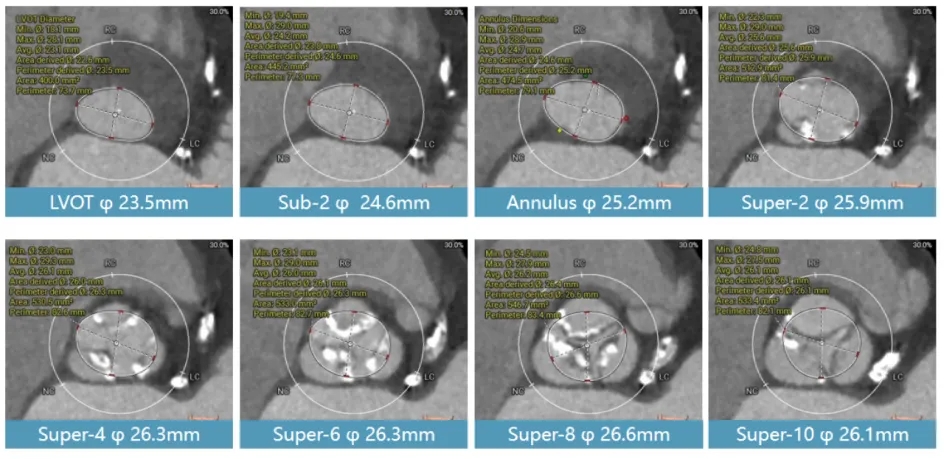

术前CT评估结果如下:患者为三叶瓣,右无窦间、左右窦间及瓣叶存在广泛钙化,钙化积分439分;瓣环径为25.2mm,LVOT:23.5mm,窦部空间可,左冠偏低,高度10.8mm;右冠脉高度可,主动脉弓大弯侧点状钙化。

多平面测量结果分析:该患者流出道较小,为倒梯形机构,瓣上结构无明显限制区域,瓣上无法提供足够封堵,预估封堵区域位于瓣环附近,钙化主要分布于瓣上,瓣环和流出道没有明显钙化,宜选择带裙边设计瓣膜,采用Taurus 26号瓣膜,可提供足够的oversize率,且带裙边设计进一步减少瓣周漏可能性,但相应起搏器风险偏大。